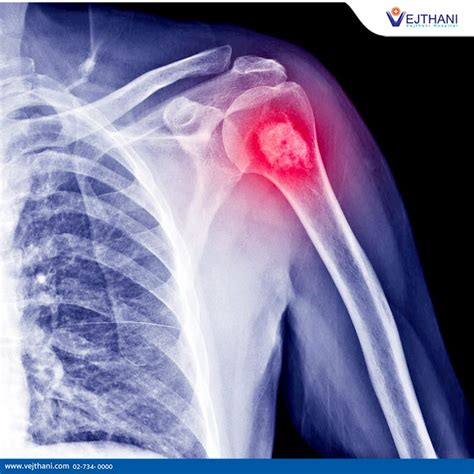

Okay, so someone’s experiencing symptoms, and they go to the doctor. What happens next? This is where the diagnosis of osteosarcoma kicks in, and it’s a bit like being a medical detective. The first step usually involves a thorough physical examination and a detailed discussion about your symptoms and medical history. The doctor will want to know about the pain, swelling, and any other changes you’ve noticed. Then comes the imaging. X-rays are often the first line of imaging when bone pain or swelling is reported. They can reveal abnormalities within the bone, such as a lytic lesion (where bone is destroyed), a sclerotic lesion (where bone is abnormally dense), or a combination of both. They can also show if the bone has been weakened or fractured. However, X-rays alone aren’t always definitive for osteosarcoma. To get a clearer picture and to assess the extent of the tumor, CT scans (Computed Tomography) and MRI scans (Magnetic Resonance Imaging) are typically ordered. CT scans are excellent for looking at the bone structure and detecting any calcifications within the tumor, and they are also used to check for metastasis to the lungs. MRI scans are particularly useful for visualizing the soft tissues surrounding the tumor and determining its exact size and boundaries, which is crucial for surgical planning. To confirm the diagnosis and determine the specific type of cancer, a biopsy is absolutely essential. This is the gold standard. A small sample of the tumor tissue is removed, either through a needle biopsy or a surgical procedure, and examined by a pathologist under a microscope. The pathologist looks for characteristic features of osteosarcoma, such as the production of osteoid by malignant cells. The biopsy not only confirms that it is osteosarcoma but also helps determine its grade (how aggressive the cancer cells appear). Sometimes, bone scans (nuclear medicine scans) are used to see if the cancer has spread to other bones. And finally, blood tests, including alkaline phosphatase levels, might be done as these can sometimes be elevated in patients with osteosarcoma. The combination of these diagnostic tools allows doctors to build a complete picture of the disease.

The Role of Imaging in Diagnosis

Imaging plays a huge role in the diagnosis of osteosarcoma , acting as our eyes to see what’s happening inside the body. X-rays are often the very first step. They’re readily available and can quickly show us if there’s something unusual going on in the bone – maybe a lesion that’s eating away at the bone, or a new, dense area forming. They can reveal classic signs like the Codman’s triangle (a small piece of bone lifted off the periosteum, the outer layer of bone, due to the tumor pushing it up) or the sunburst pattern (spicules of bone radiating outwards). However, X-rays have their limitations. To get a more detailed view, CT scans are crucial. They provide cross-sectional images, giving us a fantastic look at the bone’s internal structure and allowing us to see if there’s any calcification within the tumor. CT scans are also the go-to for checking if the cancer has spread to the lungs, which is a common site for metastasis. Then there’s MRI , which is often considered the best imaging modality for osteosarcoma of the limbs. MRI excels at showing the soft tissues. It gives us a detailed map of the tumor’s size, its precise location, and how far it has invaded into the surrounding muscles, nerves, and blood vessels. This information is critical for surgeons when planning how to remove the tumor. Think of it as providing the blueprint for the operation. Lastly, bone scans are useful for detecting if the cancer has spread to other bones in the body. They work by injecting a small amount of radioactive material that is taken up by areas of increased bone activity, like cancerous growths. Together, these imaging techniques paint a comprehensive picture, guiding the medical team towards an accurate diagnosis and a tailored treatment strategy. They help us understand the scope of the problem before we even consider a biopsy.